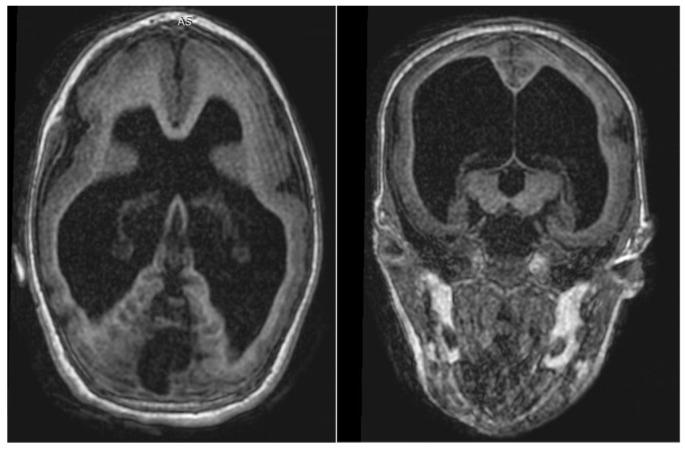

Prenatal exposure to ZIKV can cause neurologic and auditory damage. The electrophysiological responses obtained by Cortical Auditory Evoked Potentials (CAEP) may provide an objective method to investigate the function of cortical auditory pathways in children exposed to ZIKV. This case series analyzed the findings of CAEP in prenatal-period ZIKV-exposed children with and without microcephaly. The CAEP was performed in a total of 24 children. Five magnetic resonance imaging (MRI) images of the inner ear and brain of microcephalic children were analyzed and compared with CAEP measurements. Ventriculomegaly (80%), cortical/subcortical calcification (80%), and brain reduction (60%) were the most common alterations in the MRI. The P1-N1-P2 complex of the CAEP was observed in all children evaluated. The peak N2 was absent in two children. In the comparison of the CAEP measurements between the groups, children with microcephaly presented a higher amplitude of P2 ( = 0.017), which may reflect immaturity of the auditory pathways. Microcephalic and normocephalic children with prenatal exposure to ZIKV presented with the mandatory components of the CAEPs, regardless of changes in the CNS, suggesting that this population has, to some extent, the cortical ability to process sound stimuli preserved.

ZIKV 病毒的宫内感染可导致神经和听觉损伤。皮质听觉诱发电位(CAEP)的电生理反应可提供一种客观的方法,用于研究 ZIKV 暴露儿童皮质听觉通路的功能。本病例系列分析了产前 ZIKV 暴露的伴有或不伴有小头畸形的儿童的 CAEP 结果。共对 24 名儿童进行了 CAEP 检查。对 5 名小头畸形儿童的内耳和脑磁共振成像(MRI)进行了分析,并与 CAEP 测量结果进行了比较。最常见的 MRI 改变是脑室扩大(80%)、皮质/皮质下钙化(80%)和脑萎缩(60%)。所有评估的儿童均观察到 CAEP 的 P1-N1-P2 复合波。有 2 名儿童的峰 N2 缺失。在对两组 CAEP 测量值的比较中,小头畸形组的 P2 波振幅较高(=0.017),这可能反映了听觉通路的不成熟。有产前 ZIKV 暴露的小头畸形和正常头围儿童均出现 CAEPs 的必需成分,无论中枢神经系统是否发生改变,这表明该人群在一定程度上具有保留的皮质处理声刺激的能力。